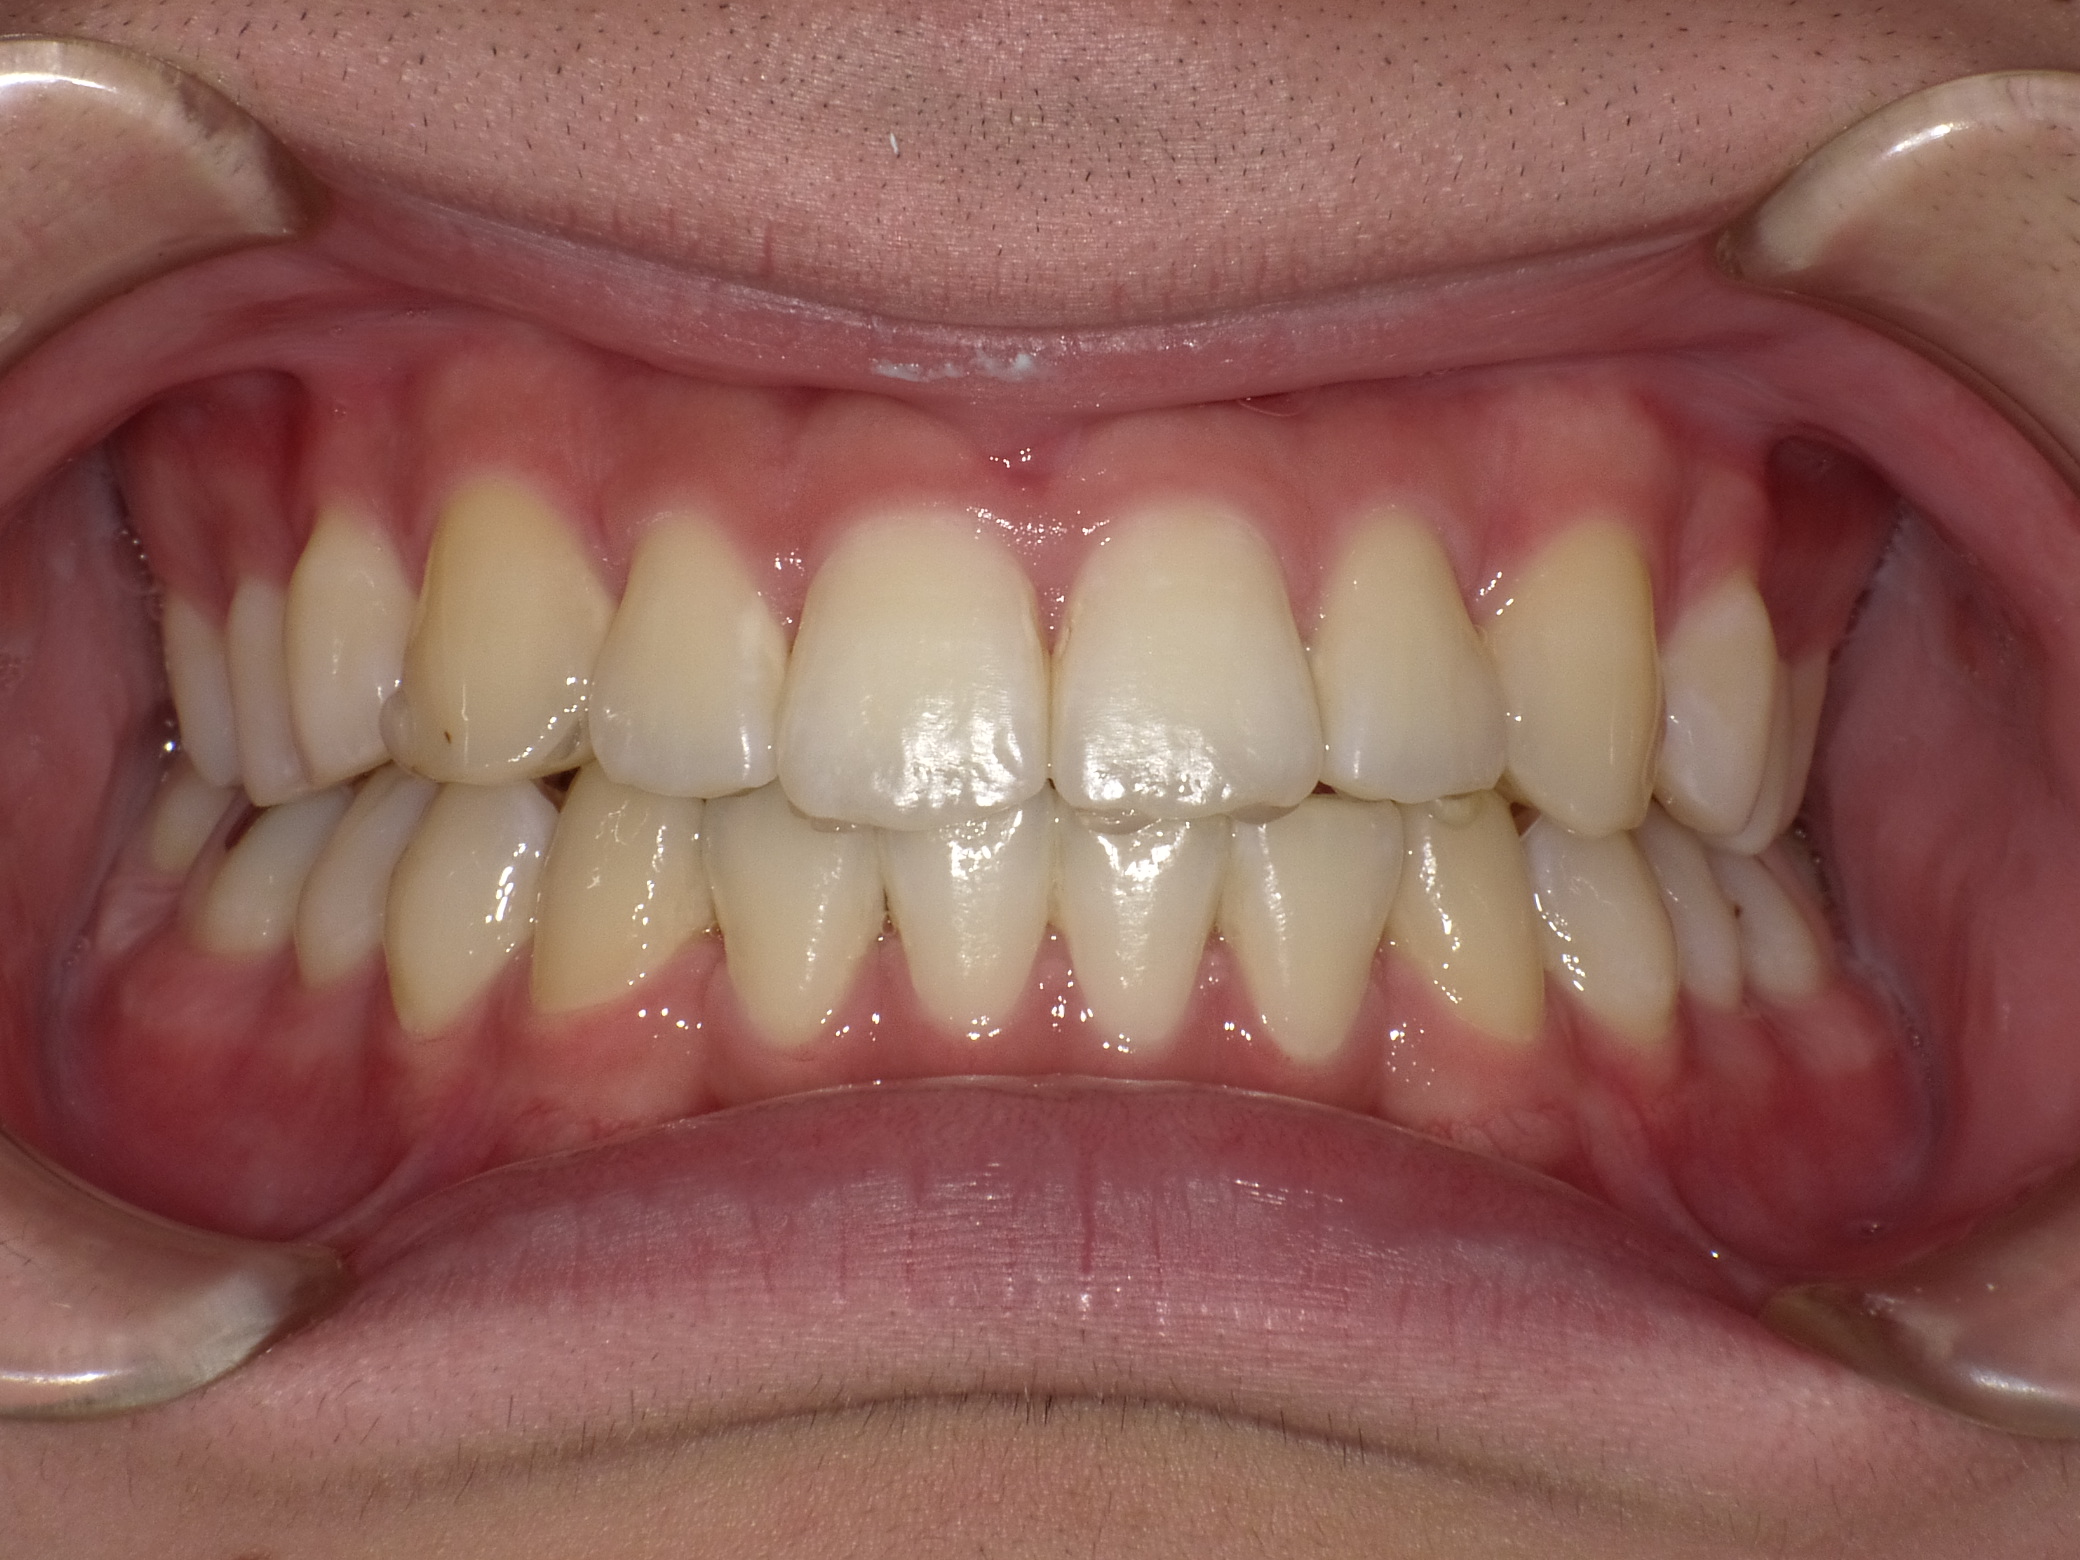

| 治療期間 | 2021年1月27日 〜2022年10月16日 |

|---|---|

| 治療費用 | 約770,000円 |

| 抜歯有無 | 抜歯なし |

| 矯正箇所 | クリアブラケット矯正 |